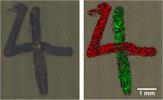

False colour Raman images are a powerful way to emphasize the distribution of chemical and structural properties within a sample. The brightness, contrast and colour of the image can help to represent material composition. By overlaying individual Raman images, you can display the distribution of multiple species or properties at the same time.

Raman image of montelukast sodium API within an oral tablet. API domains are shown in different colours for easy visualisation.

Raman image of montelukast sodium API within an oral tablet. API domains are shown in different colours for easy visualisation.